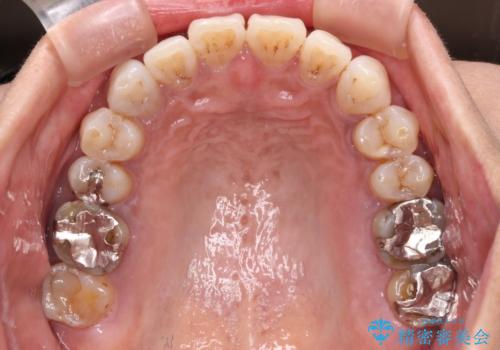

極端な上下前歯の開咬を改善 オープンバイトのインビザライン矯正

開咬の治療は、前歯を閉じるように動かすとともに、上下臼歯を圧下(骨内にめり込ませる)させることで進めて行きます。

インビザラインは臼歯の圧下を効果的に行えるため、インビザラインを用いて矯正治療を行うこととしました。

また、下顎大臼歯に根管治療が必要な歯があるため、矯正治療と並行して治療を行い、矯正後に補綴治療することとしました。